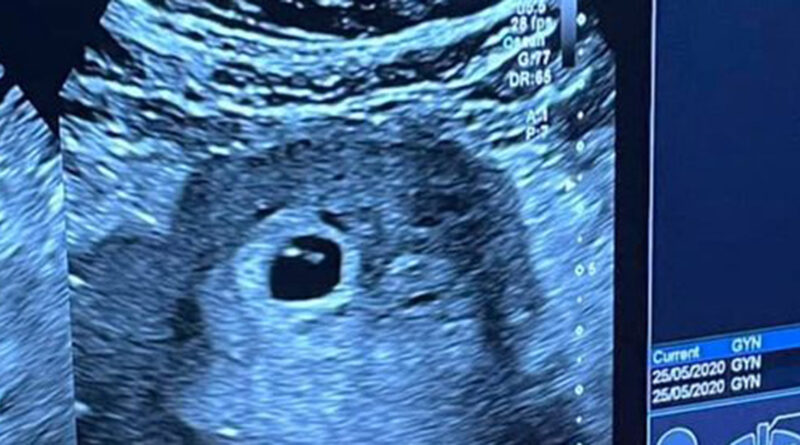

Այսօր ընդունեցինք մեր զոհված զինվորների մայրերից առաջին հղիին…

Վստահ եմ, որ ամեն օրվա հետ նրանց թիվն ավելանալու է:

Կոնկրետ դեպքում հղիությունը գրանցվել է առանց բժշկական միջամտության, բայց բոլոր նման ընտանիքների համար գործում է պետական ծրագիր: